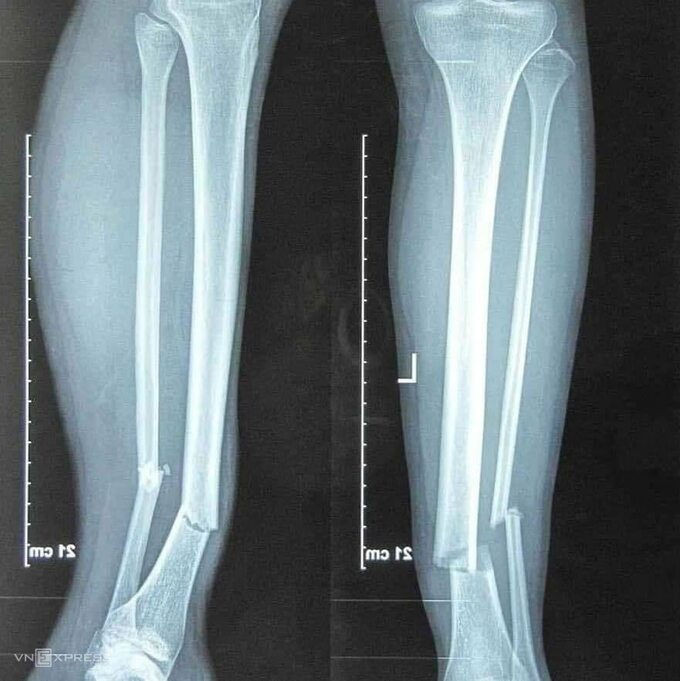

Kết quả chụp chiếu cho thấy tiền vệ của Hà Nội bị gãy một phần ba dưới xương cẳng chân phải. Anh gần như chắc chắn phải nghỉ thi đấu khoảng một năm.

Kết quả chụp chiếu cho thấy mức độ nghiêm trọng ở chân phải của Hùng Dũng.